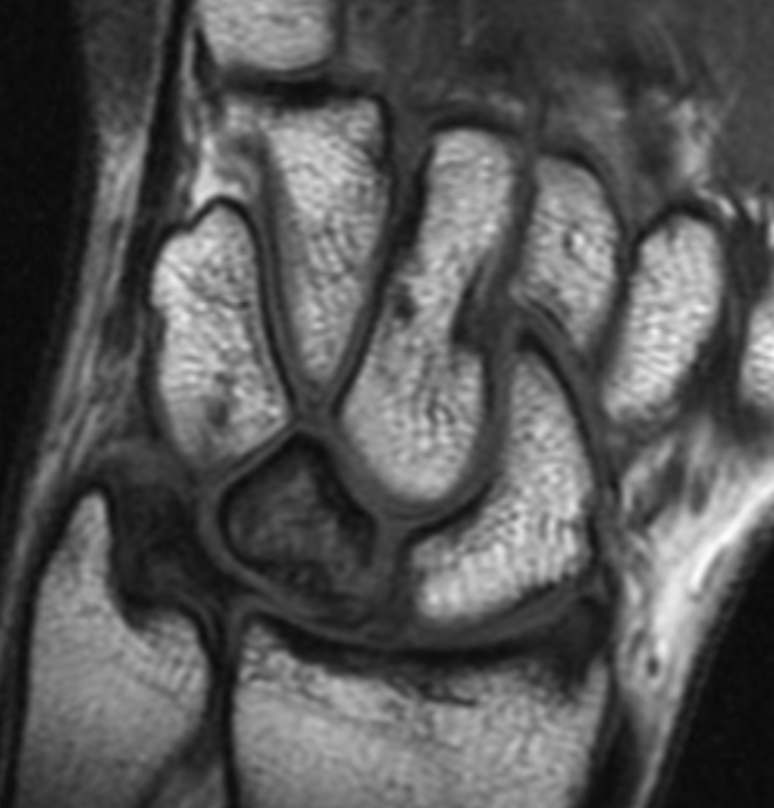

Describe the pathology indicated by the arrow (Cor PD).

Scapholunate ligament tear